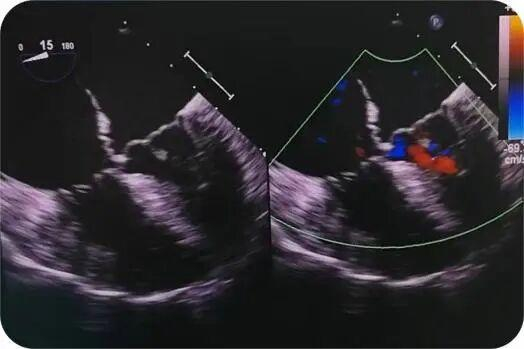

术中杨彦亮主任快速精准的为完成了原发孔房缺修补、二尖瓣成形、三尖瓣成形,术中食道超声提示房缺缝合确切、瓣膜成形满意。麻醉科、手术室等各科室团结协作,为手术的顺利进行提供保障。术后在医护团队的精心照料下,当天撤离呼吸机支持,术后一周顺利出院。